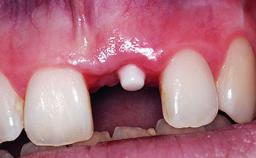

A 30-year-old patient presented at our clinic with a chief complaint of pain in her endodontically treated right maxillary central incisor (tooth 11) with a post-and-core and a fixed single crown. She had a very high lip line, a medium to thin soft-tissue phenotype, and a medium scalloped gingival contour. She also had high esthetic expectations because of her young age and beautiful smile. However, her expectations were realistic and she understood the risks of the treatment. At the initial clinical examination there was a slight mobility of tooth 11; no fistula was observed. The patient also had a single crown on the adjacent tooth 21. Both restorations were old and esthetically deficient. A digital periapical radiograph showed a very small periapical radiolucency, a thick intraradicular post, and no separation between root fragments.

Placement Protocol Early or late implant placement